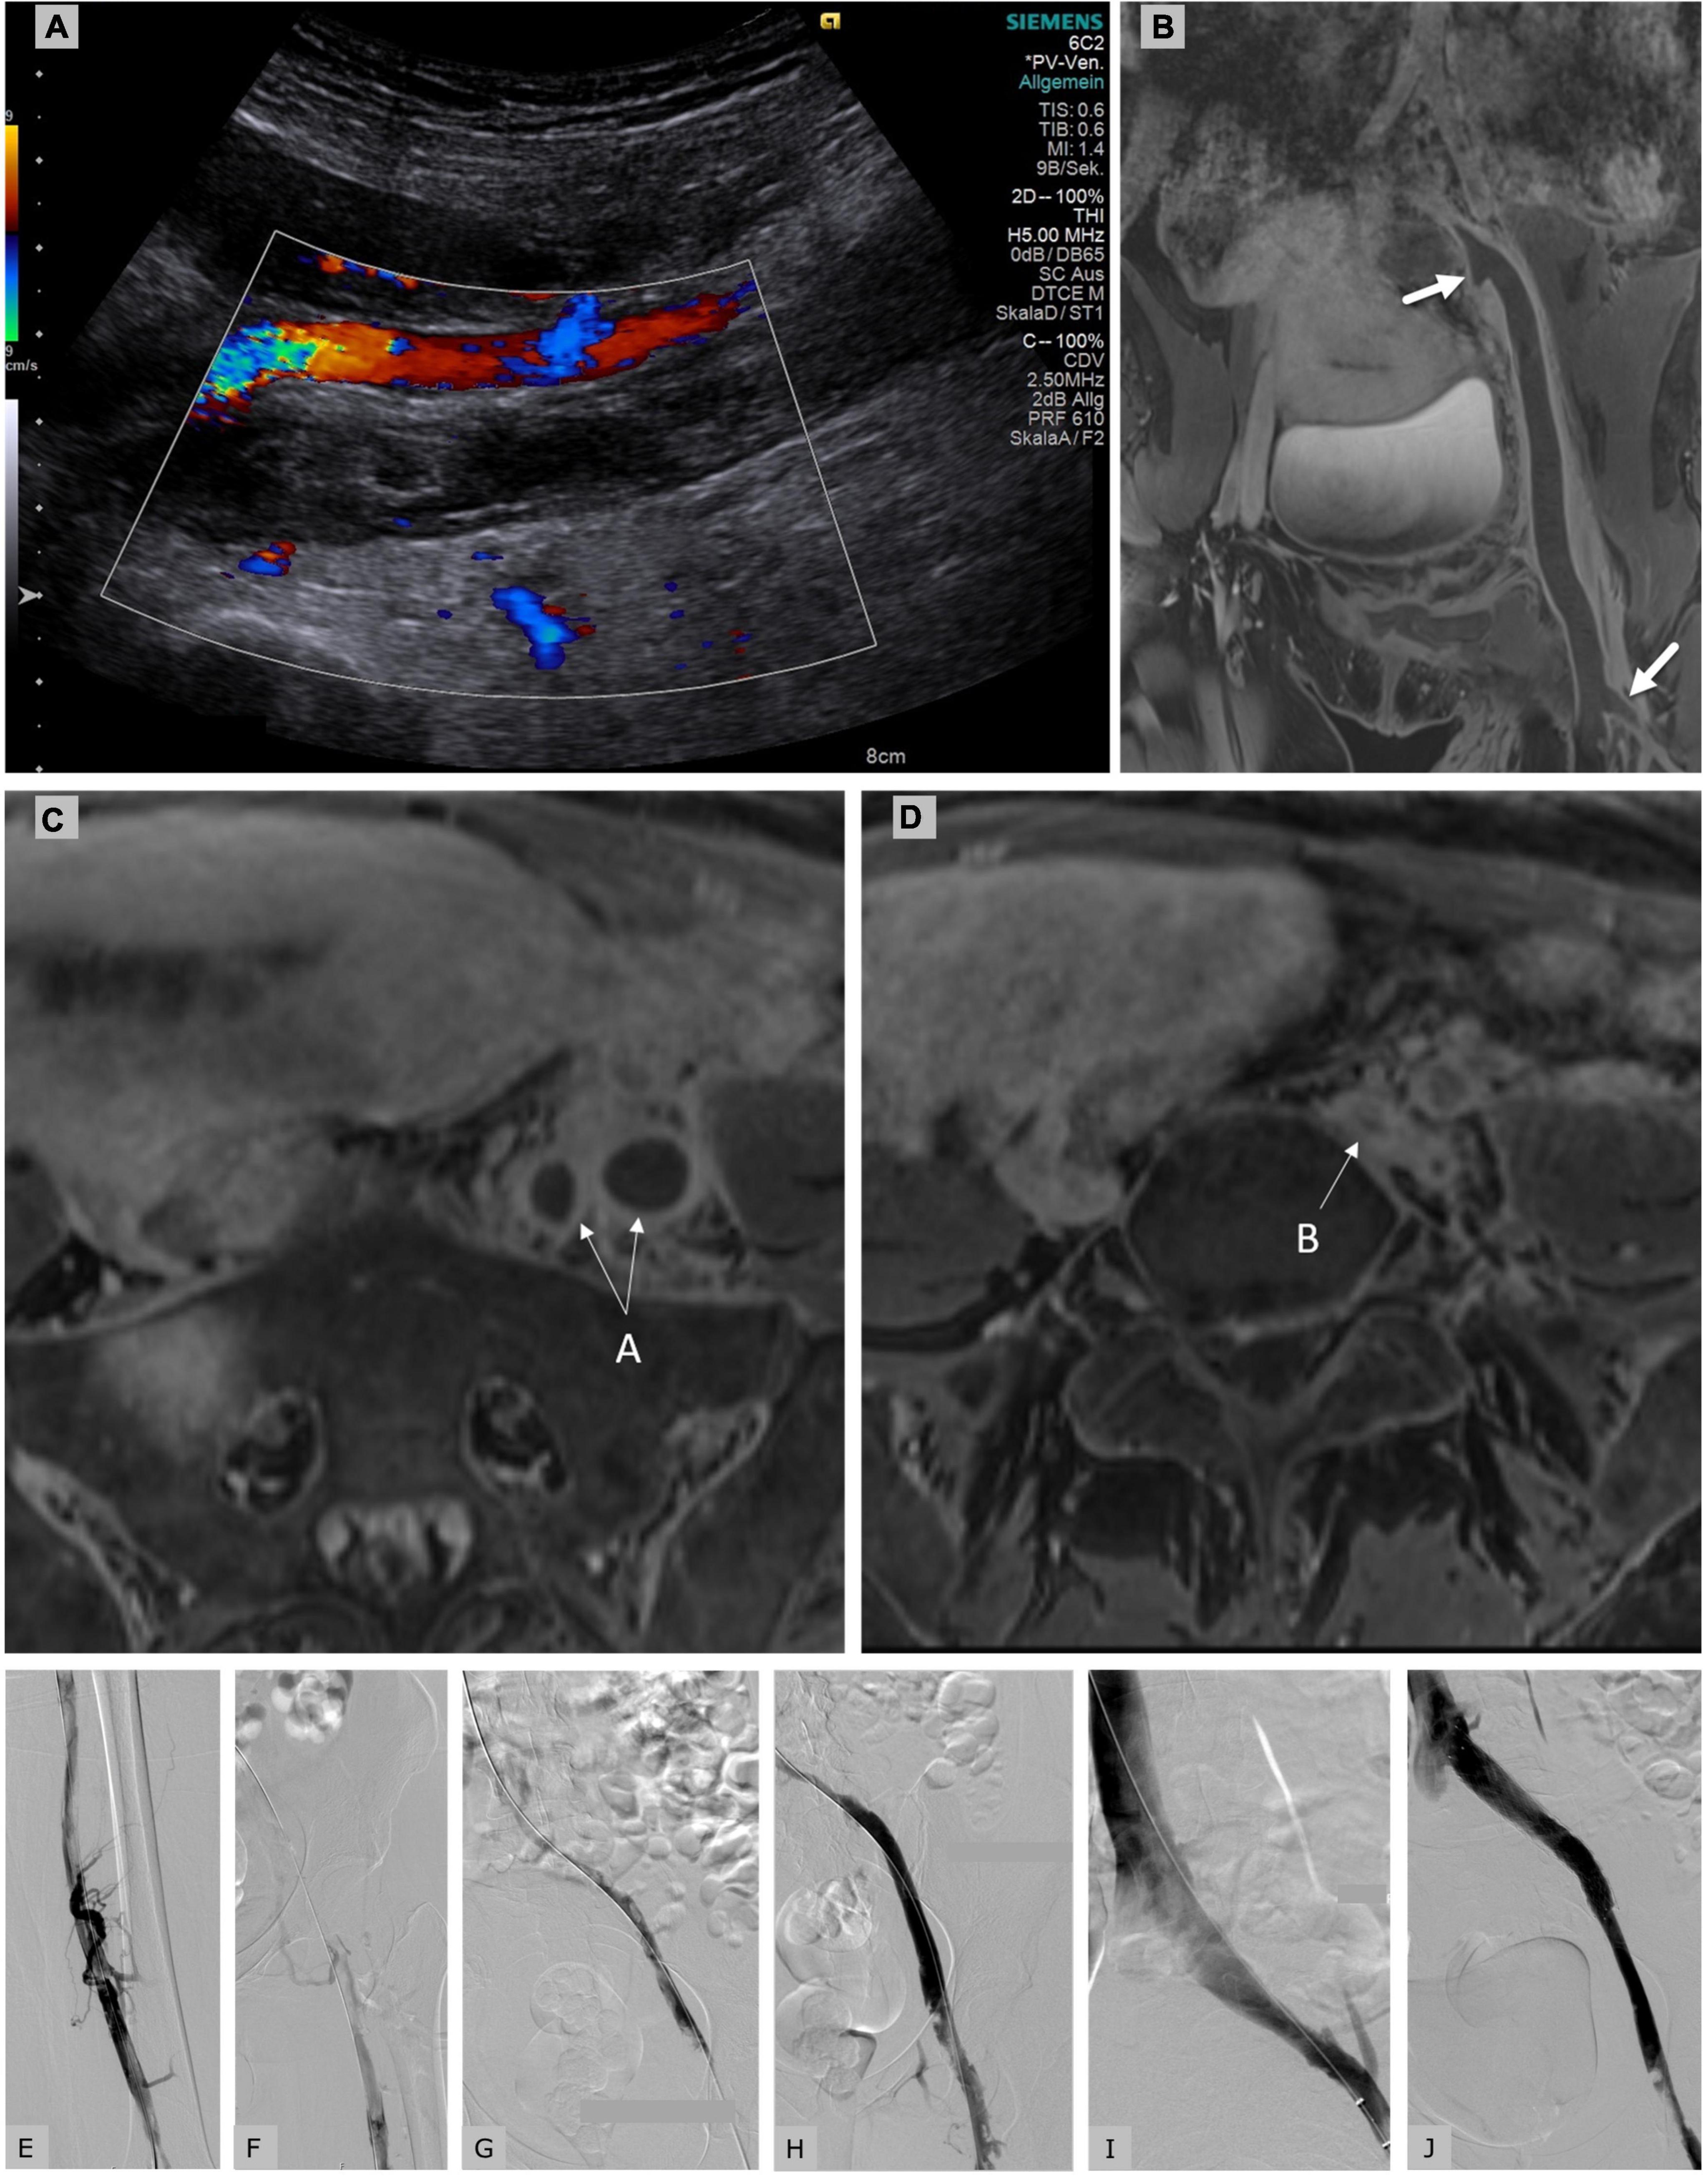

(PDF) Successful catheter directed thrombolysis in postpartum deep Catheter-Directed Thrombolysis For Deep Vein Thrombosis 2021 Update    venous thromboembolism (vte), which includes pulmonary.  if left untreated, dvt increases the risk of pulmonary embolism (pe), recurrent venous thromboembolism (vte), and post.   catheter directed thrombolysis (cdt) has evolved as a treatment modality for patients diagnosed with proximal and. Catheter-Directed Thrombolysis For Deep Vein Thrombosis 2021 Update.